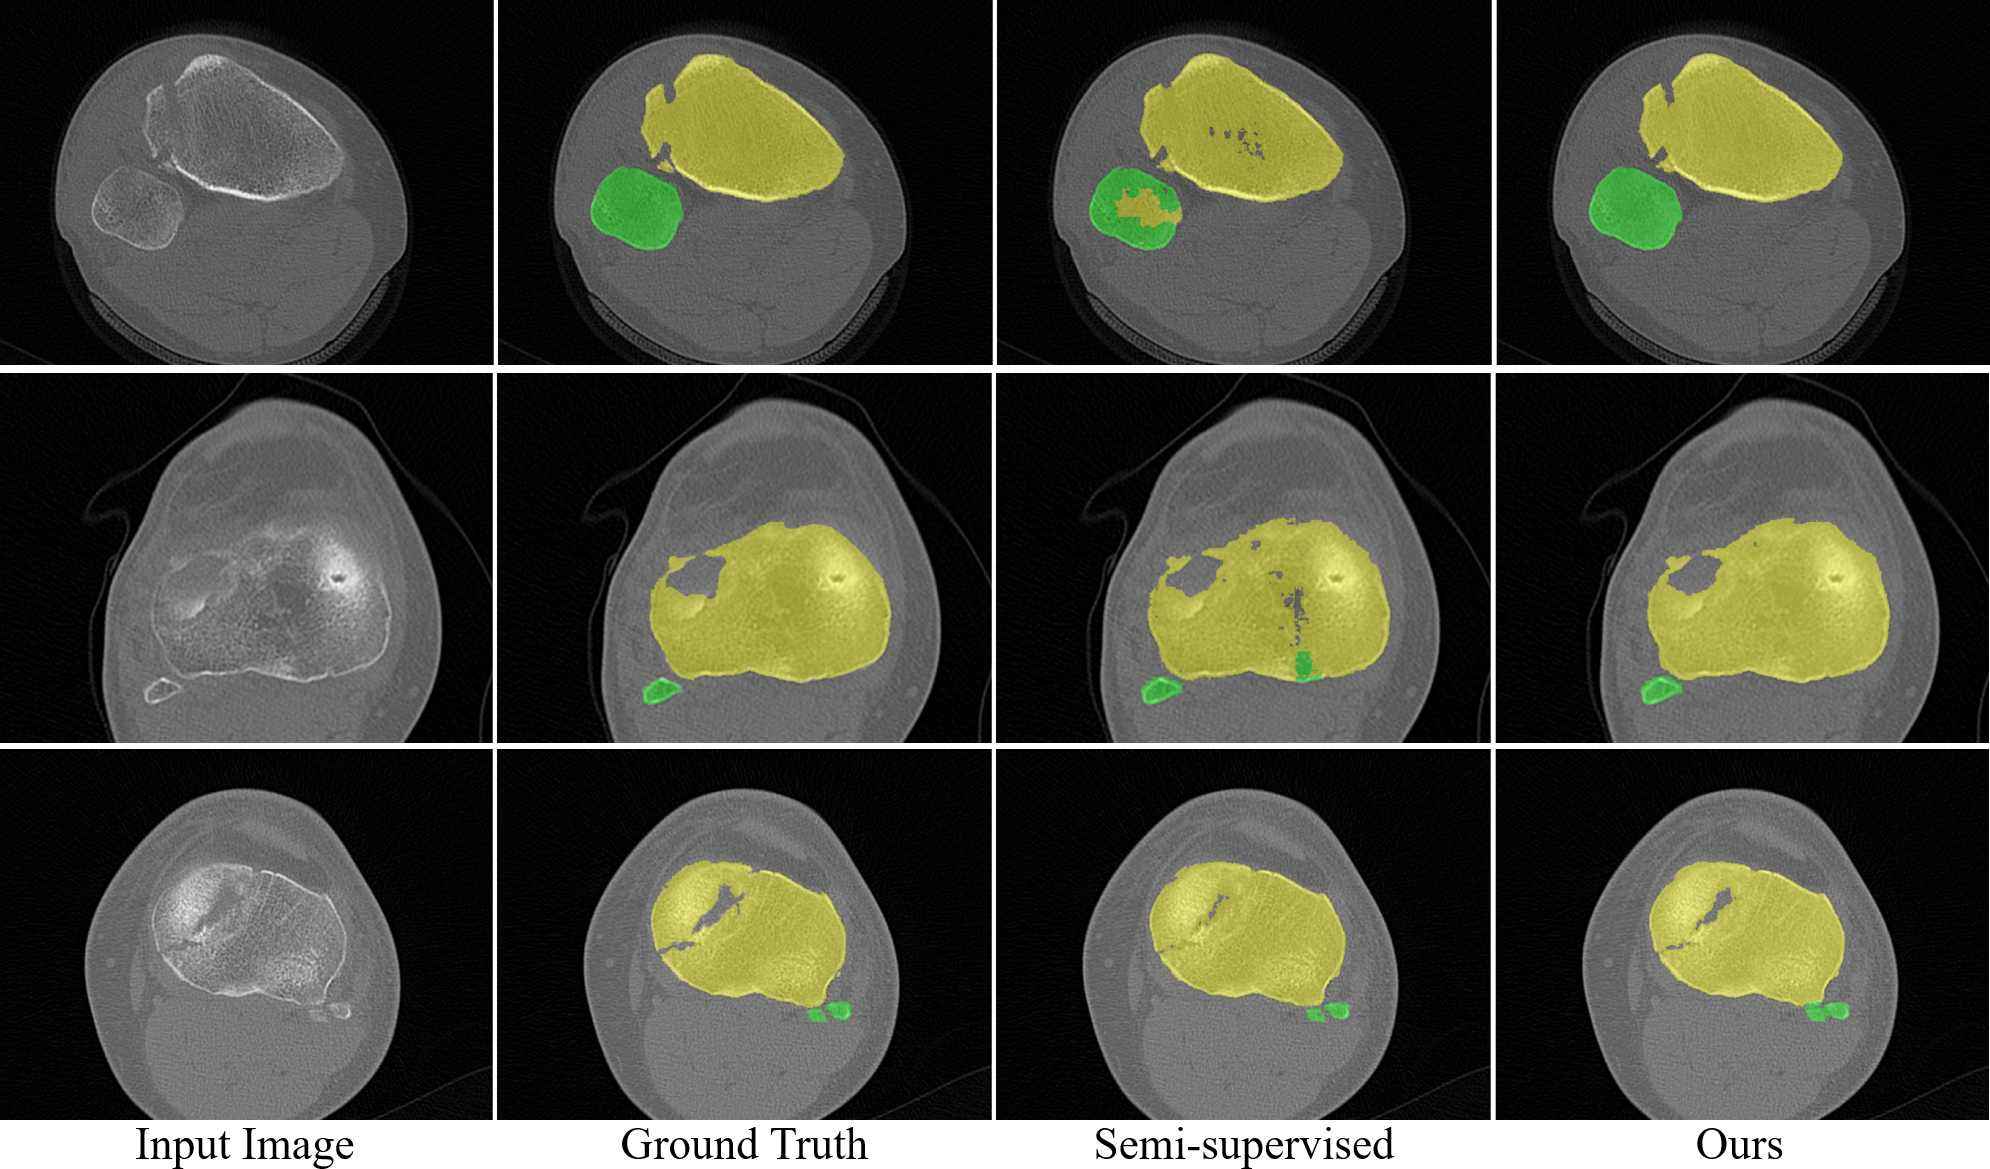

Refer to caption

Figure 6: 2D visualization of the segmentation results for tibial plateau fractures.

Fig. 5 shows the 3D visualization of segmentation results between semi-supervised learning and our method. It is obvious that our method provides more accurate segmentation results. Fig. 6 further visualizes some detailed 2D comparisons, showing that our method produces segmented boundaries most similar to the ground truth. Even in cases with complex fracture morphologies, our method demonstrates a strong ability to accurately segment skeletal structures.